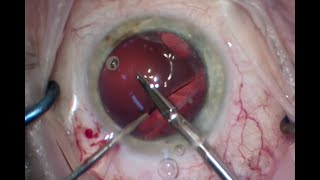

Dr Cronin provides these videos as an educational resource for training ophthalmologists, other ophthalmologists and patients. Dr Cronin specialises in corneal and anterior segment diseases including LASIK, laser eye surgery, cataracts, keratoconus, Fuchs endothelial dystrophy and pterygium surgery.